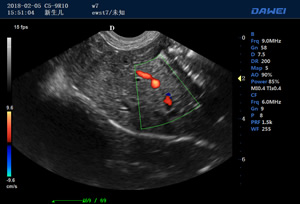

出色的獸用臨床應用

·支持B、C、PW、CW、寬景成像

·適用于各種動物的臨床腹部、胸腔,心臟、肌腱、小器官、眼球、生殖系統等的檢查